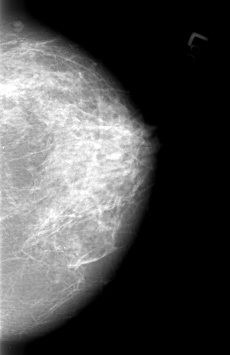

ics_version 1.0 filename B-3012-1 DATE_OF_STUDY 23 5 1995 PATIENT_AGE 53 FILM FILM_TYPE REGULAR DENSITY 3 DATE_DIGITIZED 24 4 1997 DIGITIZER LUMISYS LASER SEQUENCE LEFT_CC LINES 4256 PIXELS_PER_LINE 2752 BITS_PER_PIXEL 12 RESOLUTION 50 NON_OVERLAY LEFT_MLO LINES 4336 PIXELS_PER_LINE 2696 BITS_PER_PIXEL 12 RESOLUTION 50 NON_OVERLAY RIGHT_CC LINES 4136 PIXELS_PER_LINE 3152 BITS_PER_PIXEL 12 RESOLUTION 50 OVERLAY RIGHT_MLO LINES 4216 PIXELS_PER_LINE 3192 BITS_PER_PIXEL 12 RESOLUTION 50 OVERLAY |